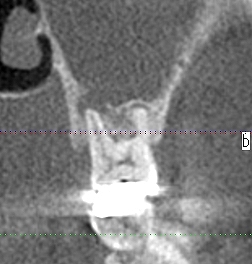

術前のCTになります

根尖病巣が認められます

根尖病巣が上顎洞にはじけているのが確認できます

炎症が上顎洞に波及しているのがわかりました

ここまで大きな白く映っている炎症を引き起こしているのがこの歯になることが術前からわかりました